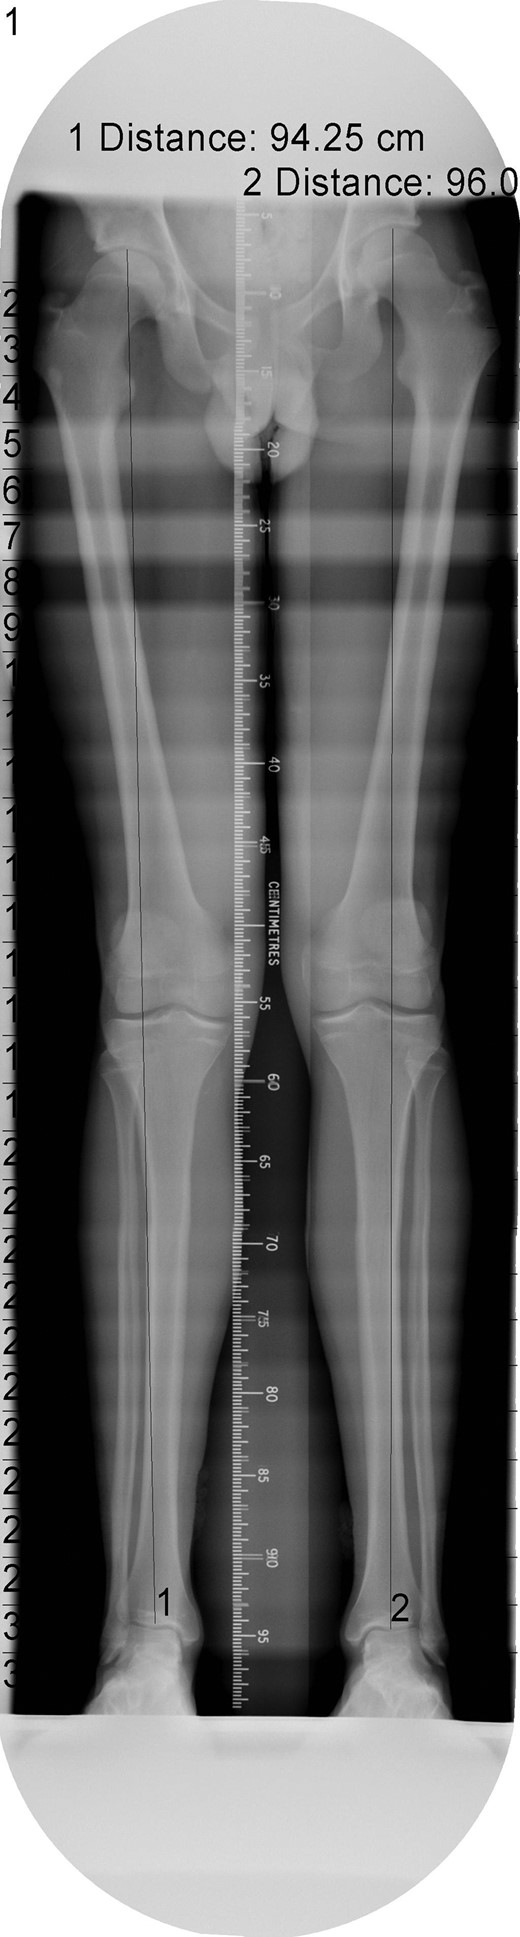

The patient's initial management was non-operative with a period of knee protection with a range of movement brace and intensive rehabilitation. Approximately 3 months after the index injury he returned to competitive football but shortly after his return sustained a further valgus injury and despite further conservative treatment was unable to return to sport. He was referred to our service with ongoing instability symptoms. Upon clinical assessment we noted an asymmetric valgus alignment of the knee and abnormal laxity of the MCL. Radiographic investigations revealed an abnormality of the lateral distal femur and alignment radiographs confirmed the valgus mal-alignment with abnormal opening of the medial tibio-femoral joint space on single-leg stance radiographs (Figs 2–4). We obtained the patient's MRI scan and reviewing this with Radiology colleagues revealed subtle changes of increased lateral femoral physis fluid density on T-2 weighted images consistent with a Salter Harris Type V injury (Fig. 5).

Long-leg alignment radiograph showing valgus deformity of the right knee.